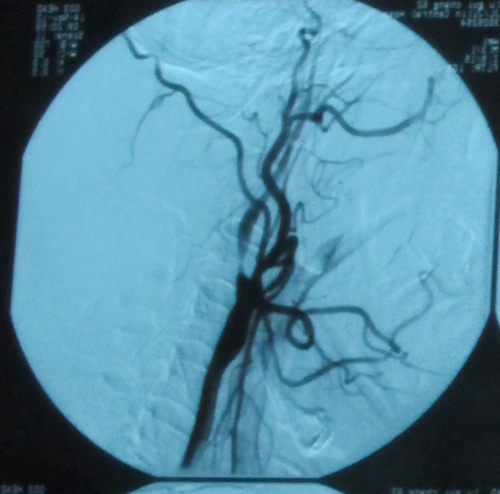

2012年11月25日,北京安贞医院脑卒中中心主任、中美脑中风协作组中方组长张勤奕教授受邀于吉林市中心医院为一例重度颈动脉狭窄患者施行了颈动脉内膜剥脱术,手术圆满成功。

患者卢某某,男性,62岁,主因“发现血管狭窄1月”入院。患者一月前因头晕到附属医院做颈部血管B超发现血管狭窄,左颈动脉重度狭窄,走路不稳,无言语不清,无肢体活动不灵,无头痛,无恶心、呕吐,无视物成双,无耳鸣耳聋,无吞咽困难,无意识障碍及抽搐发作,门诊以“左颈动脉重度狭窄”收住院。患者既往冠心病史6年,高血压3年,心脏支架2个。

入院后行DSA检查,证实上述诊断,2012年11月25日,张勤奕教授受邀于吉林市中心医院为其施行了颈动脉内膜剥脱术,手术圆满成功,患者恢复良好。